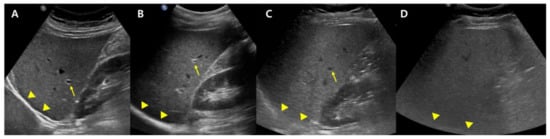

B-mode US allows an estimate of steatosis severity according to the subjective examination of sonographic patterns [20]. The severity is generally categorized as absent, mild, moderate, and severe. Mild hepatic steatosis is seen as a more diffuse increase in liver echogenicity than the renal cortex, moderate hepatic steatosis is seen as an increase in liver echogenicity with impaired visibility of the diaphragm and portal vein wall, and severe hepatic steatosis is seen as a large increase in liver echogenicity and poor visualization of the diaphragm, portal vein wall, and posterior regions of the right liver lobe (Figure 1).

Figure 1.

Conventional US examination for evaluation of hepatic steatosis: normal (A), mild (B), moderate (C), and severe (D) hepatic steatosis. The vessel (arrow) and diaphragm (arrowhead) are well distinguishable in a normal liver (A). Liver parenchymal echogenicity is increased compared with renal cortical echogenicity in mild hepatic steatosis (B). In moderate hepatic steatosis (C), the vessel wall echo becomes obscured (arrow), and the diaphragm is partially visible (arrowhead). Due to a marked increase in liver echogenicity in severe hepatic steatosis (D), there is blurring and poor visualization of the diaphragm (arrowhead), as well as deep posterior parts of the right liver lobe.

US can offer reasonable accuracy in detecting moderate to severe hepatic steatosis with a sensitivity and specificity of about 90% and 95%, respectively, for patients lacking concomitant chronic liver disease [18,20]. Nevertheless, it has a mere moderate diagnostic ability in detecting hepatic steatosis of 5% or greater (mild steatosis; sensitivity, 50–62%). Further, it may not succeed in overweight patients or patients with ascites; the modality is strongly operator- and platform-dependent [21].